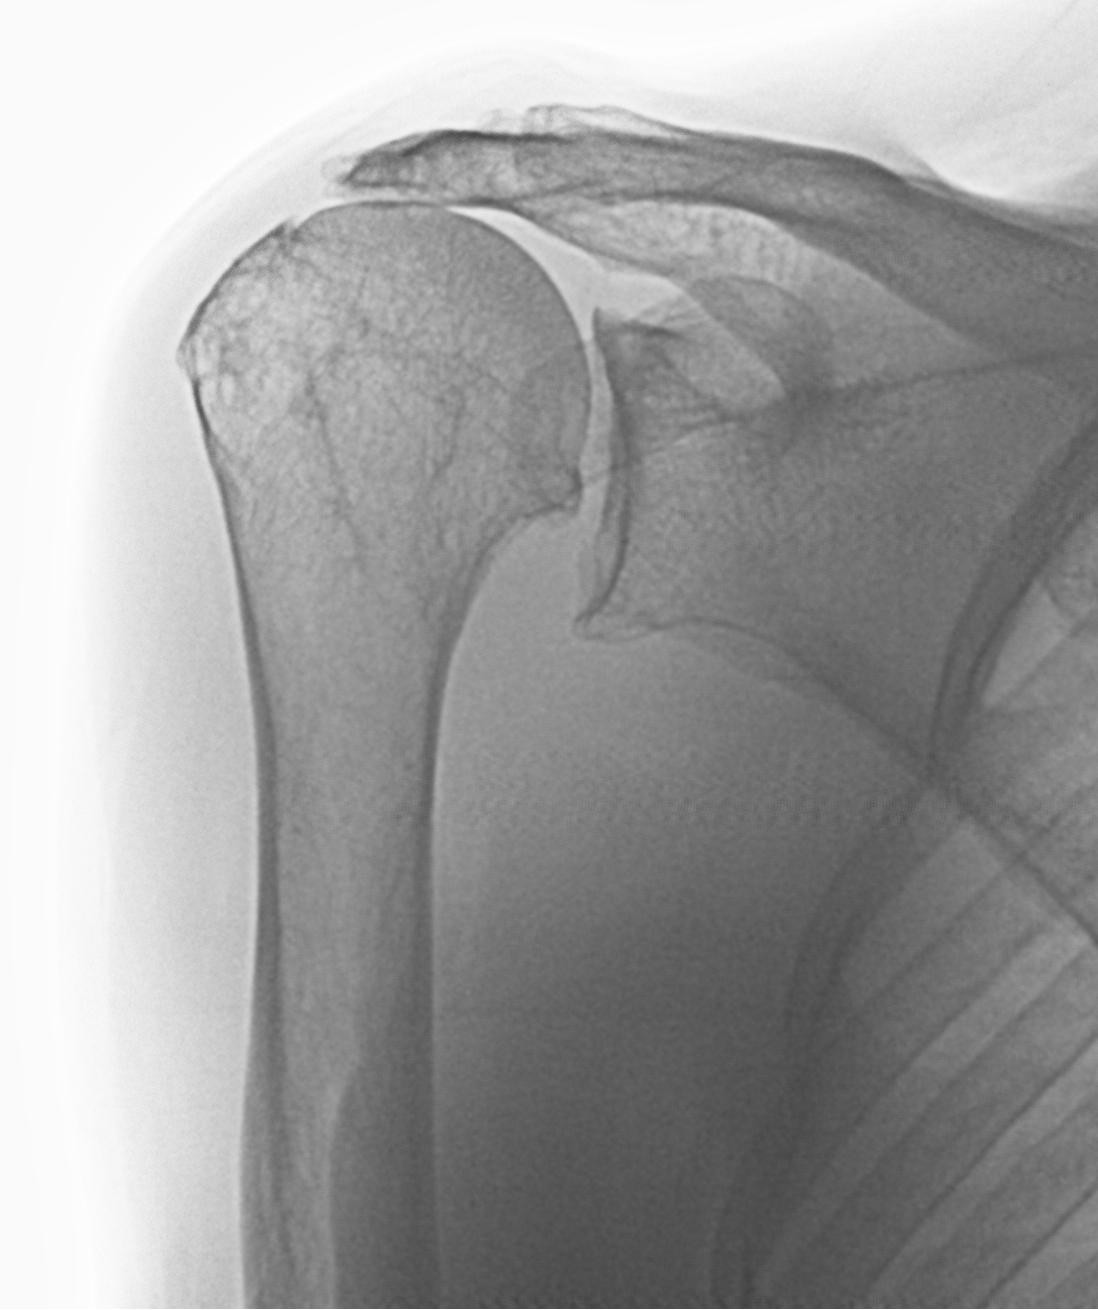

From www.jsesinternational.org

MRI findings of traumatic and degenerative rotator cuff tears and Rotator Cuff Tear Degenerative  Injuries to the shoulder, such as falling on. An acute tear or a degenerative tear. Rotator cuff tears are a very common source of. This review describes the epidemiology and natural history of degenerative. Rotator cuff injuries are most often caused by progressive wear and tear of the tendon tissue over time. The pathogenesis of these tears is still partly. Rotator Cuff Tear Degenerative.